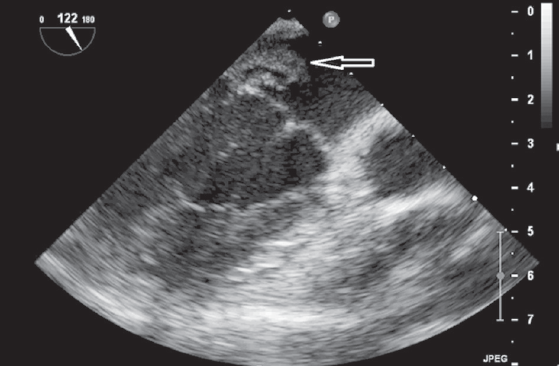

По результатам ЭхоКГ от 31.12.14 — сократительная способность миокарда сохранена. Фракция выброса левого желудочка 65 %. Камеры сердца не расширены. В области передней и задней створок митрального клапана визуализируются крупные и множественные мелкие вегетации. Недостаточность митрального клапана 1–2-й степени. Относительная недостаточность трикуспидального клапана 1–2-й степени. Умеренные явления перикардита (рис. 3, 4).

Рис. 3. Эхокардиограмма пациентки А., 16 лет. Апикальная 4-камерная проекция. Вегетации на передней створке митрального клапана

Fig. 3. ECHO of 16-year old female patient A. The apical 4-chamber view. Vegetations on the aortic leaflet of mitral valve

Чреспищеводная ЭхоКГ: визуализирована большая вегетация, длиной более 1 см, фиксированная своим основанием к задней сворке МК и вегетации на передней створке МК (рис. 5, 6).

Рис. 5. Чреспищеводная эхокардиограмма пациентки А., 16 лет. Продольная ось сердца. Стрелками указаны вегетации на задней створке митрального клапана

Fig. 5. Transesophageal ECHO of 16-year old female patient A. Long axis. Arrows indicate vegetations on the mural leaflet of the mitral valve